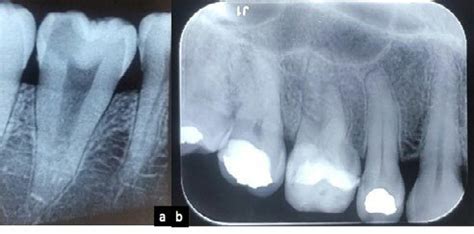

Otro avance revolucionario fue la introducción de las radiografías dentales a finales del siglo XIX. Durante el siglo XIX, se perfeccionaron los materiales utilizados para tratar las caries dentales y restaurar dientes dañados. La amalgama, una aleación compuesta principalmente por mercurio, plata, estaño y cobre, comenzó a utilizarse ampliamente a partir de la década de 1830. En 1815 se comenzaron a utilizar los fluoruros para la prevención de caries y en 1844 se empezaron a fluorar las aguas potables para reducir las caries.

Una de las primeras radiografías dentales.